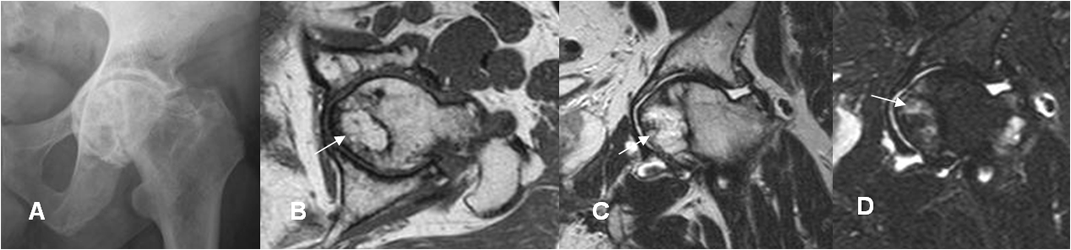

Fig 83 A. Osteonecrosis clase B.

A: Rx AP. Alteración en la densidad de la cabeza femoral. Adicionalmente hay signos de coxa profunda y sobrecubrimiento acetabular posterior, por pinzamiento tipo CAM.

B: RM axial en T1, B: RM coronal en T2 y D: RM coronal en STIR. Se identifica lesión geográfica en la parte interna de la cabeza femoral, hiperintensa en T1 y T2, con edema trabecular en algunas zonas, por osteonecrosis clase B.